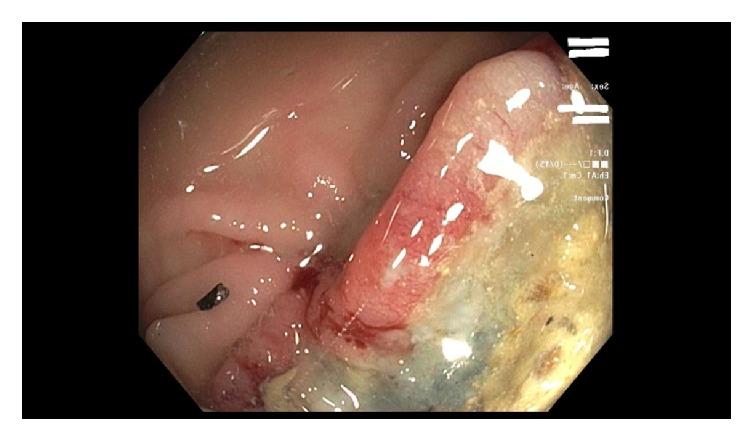

胃结肠瘘:结肠癌的一种罕见表现。

Gastrocolic Fistula: A Rare Presentation of Colon Cancer.

Gastrocolic fistulae have been described for benign conditions including penetrating peptic ulcer and complicated pancreatitis. Malignant etiology can arise from gastric or colon cancer and is a rare and late complication with an incidence of 0.3-0.4%. Usual presentation is the classic triad of weight loss, diarrhea, and feculent vomiting. Barium enema has been shown to have the highest diagnostic accuracy but endoscopy offers additional advantage of biopsy to aid in diagnosis of malignant etiology; the role of computed tomography (CT) scan is controversial. Treatment by one-stage en bloc surgical approach is the current acceptable standard of care with variable recurrence and survival rates. Adjuvant chemotherapy would be based on lymph node involvement and patient discussion.

摘要